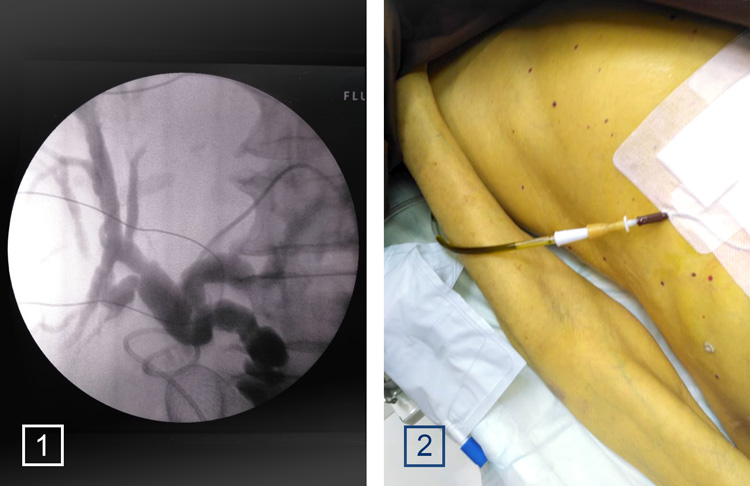

1 - холангиоскопия (эндоскопического исследования желчных протоков) при проведении чрескожного чреспеченочного дренирования левого долевого желчного протока

2 - у пациента выраженная желтушность кожного покрова. Для устранения патологии внутрь печеночного протока установлен дренаж